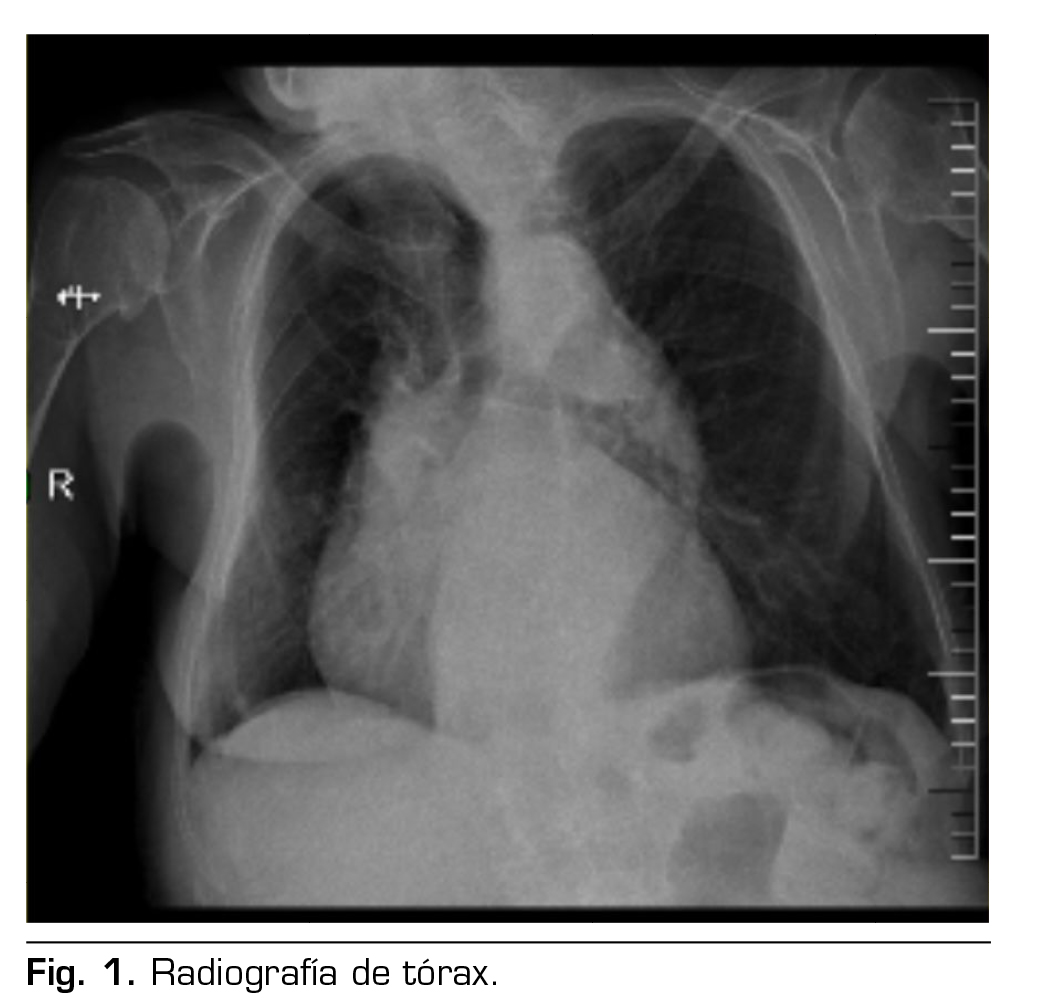

Figura 1